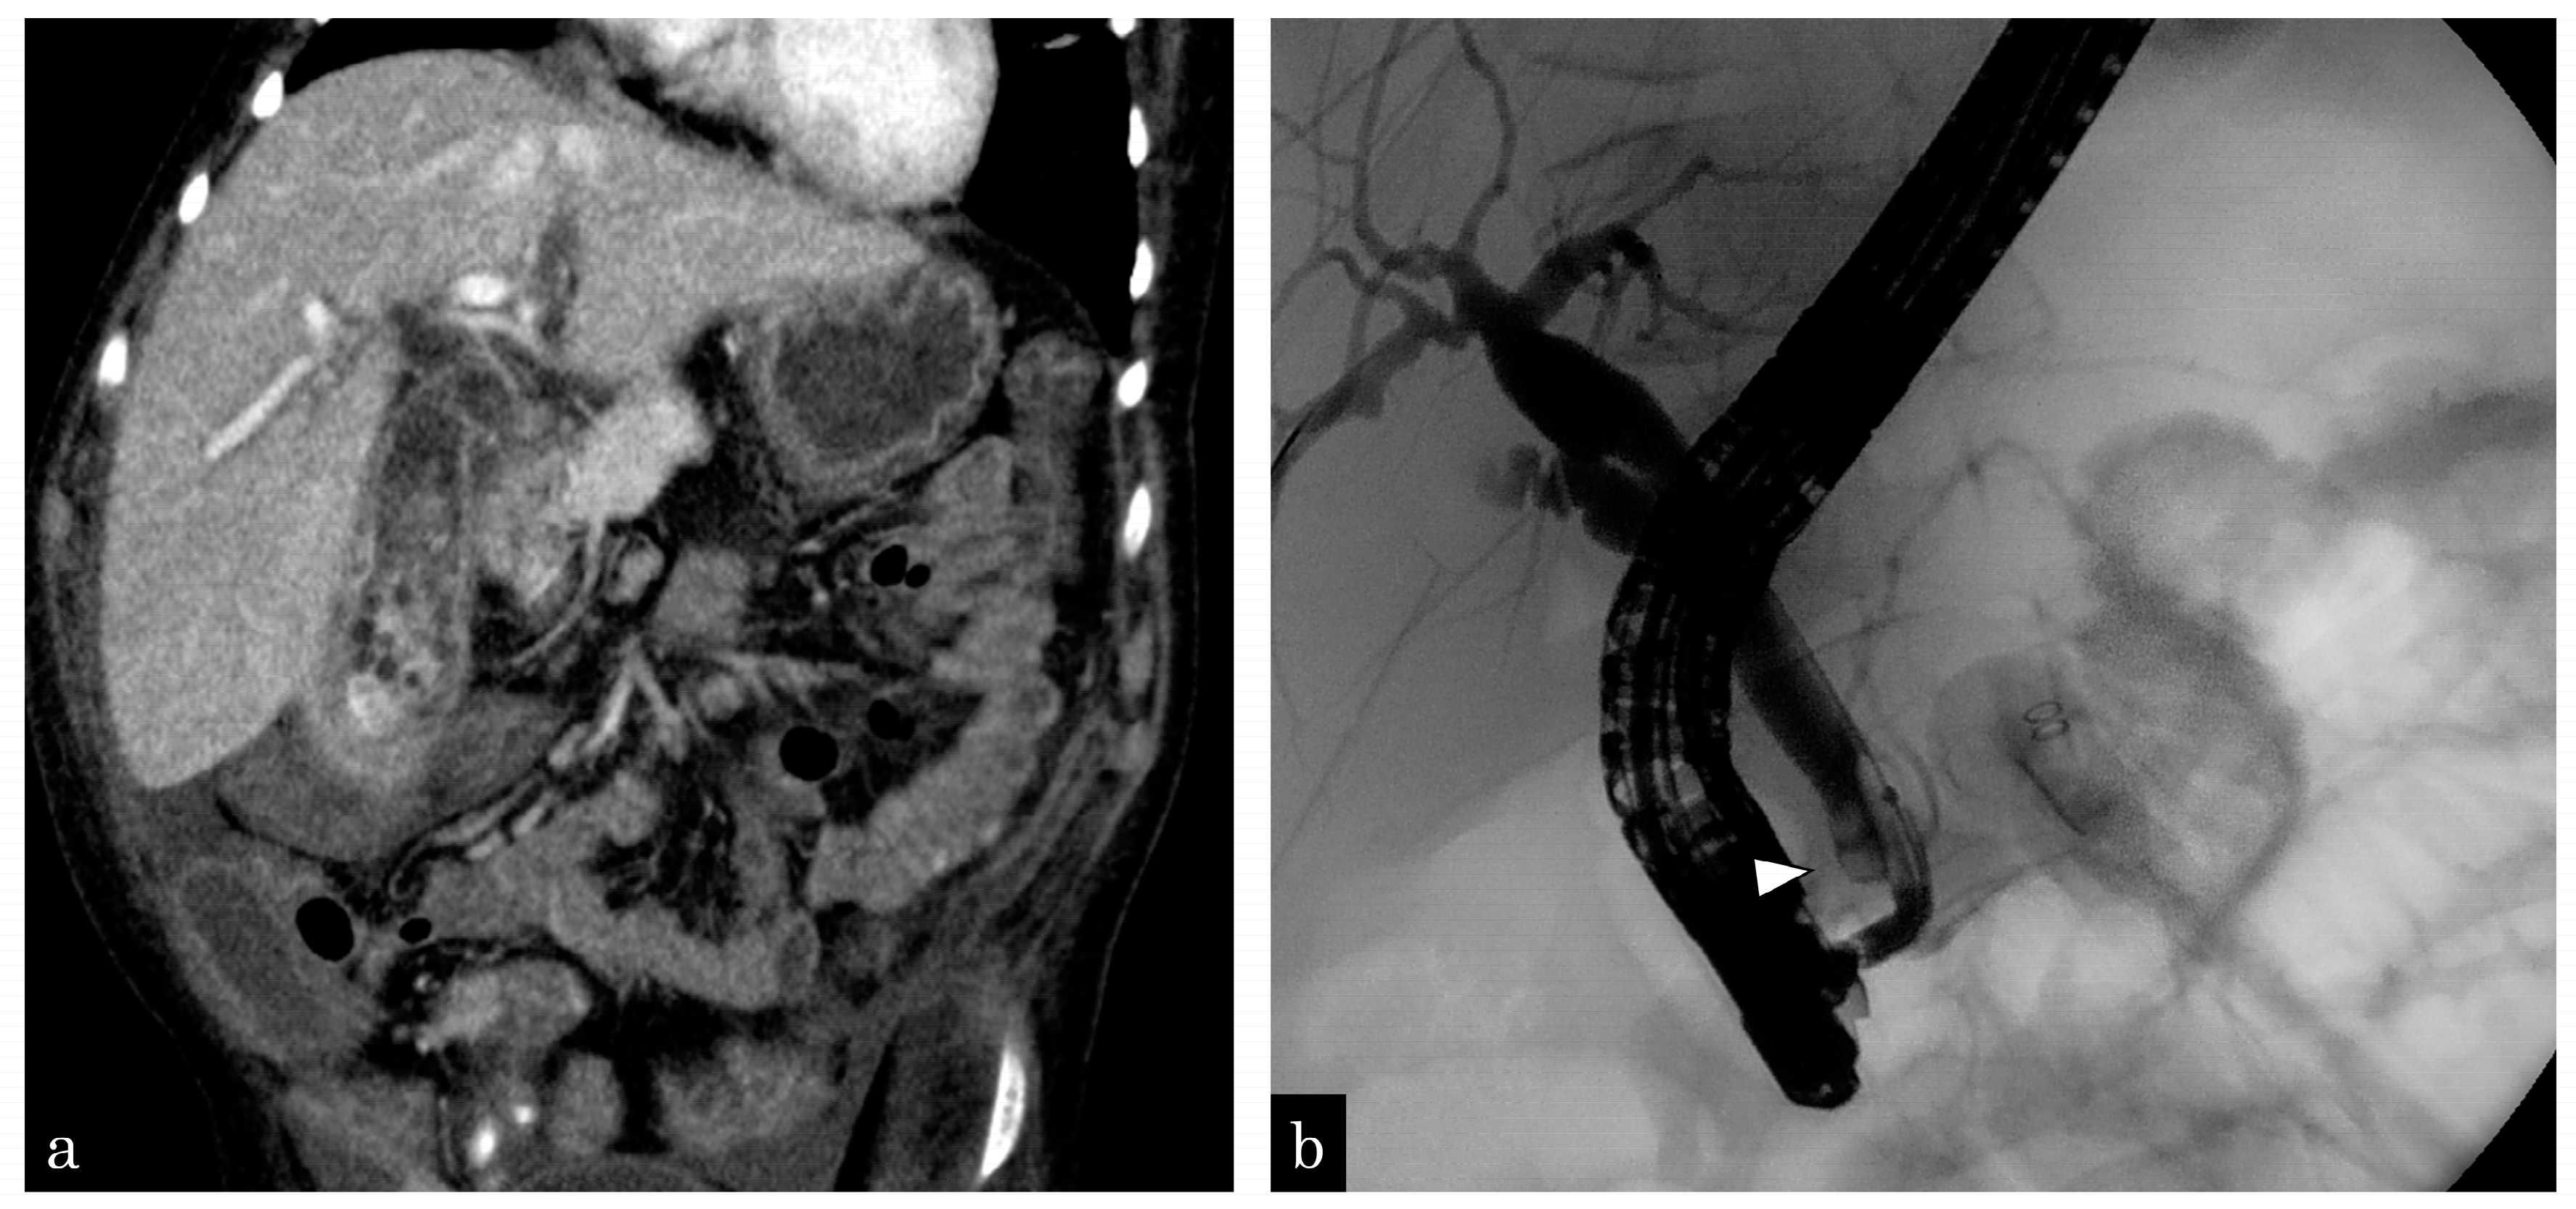

An 8-year-old boy with trisomy 13 complained of jaundice and abdominal pain. Computed tomography revealed gallbladder wall swelling and multiple stones in the gallbladder and CBD (Figure 3a). Percutaneous transhepatic gallbladder drainage and ENBD tube insertion were performed for cholangitis and bile stones. After the improvement of cholecystitis, the patient simultaneously underwent laparoscopic cholecystectomy and EPBD. During surgery, 55 small bile stones in the gallbladder and 2 stones in the CBD were observed (Figure 3b). All bile stones were removed twice via EPBD, using a balloon catheter. One day after EPBD, lipase levels increased to 4999 IU/L but returned to normal on the second day. Five years have passed since the surgery and EPBD and no complications have been observed.

Figure 3.

An 8-year-old boy complained of gallbladder and common bile duct stones. (a) Enhanced computed tomography (CT) revealing multiple small gallstones and gallbladder swelling. (b) The patient has developed septic shock due to cholangitis. Emergency gallbladder drainage is performed, and a bile stone impacting the distal common bile duct (white arrowhead) is observed. A 4-Fr ENBD tube is inserted.